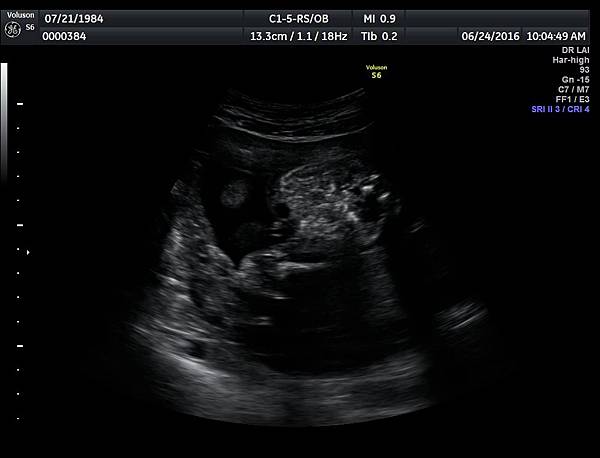

6月24日在我的診所,我幫一位懷孕22週31歲的孕婦看高層次超音波,發現胎兒的腸子很白,形狀也特別的怪( 附圖 1~12 ),我建議她做進一步相關的檢查,包括抽羊水檢查等等。